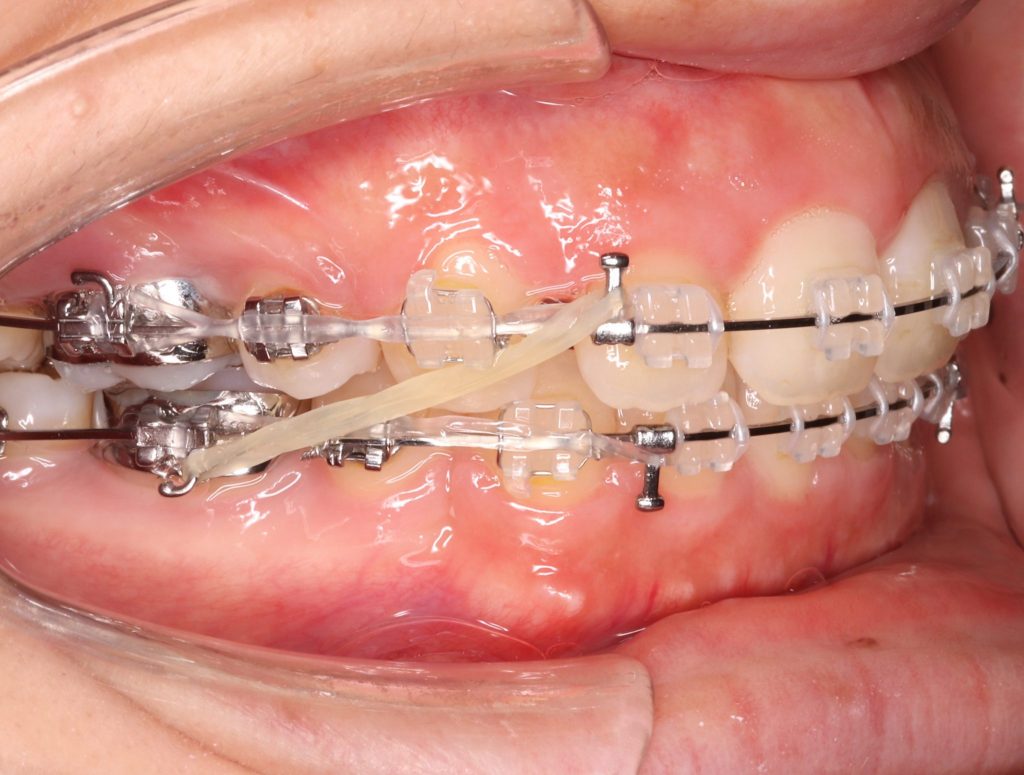

ゴムかけとは

歯列矯正治療を行う際に矯正装置(マウスピースやワイヤーなど)に

ゴムをかけることで、矯正力の補助的な力を歯に加える方法です。

ゴムかけは歯を引っ張る時や噛み合わせを合わせていく時

などに行うことが多い処置内容です。

ゴムの牽引力により、

矯正装置だけではかけられない力を歯にかけることで

適切な噛み合わせを作ることが可能になります。